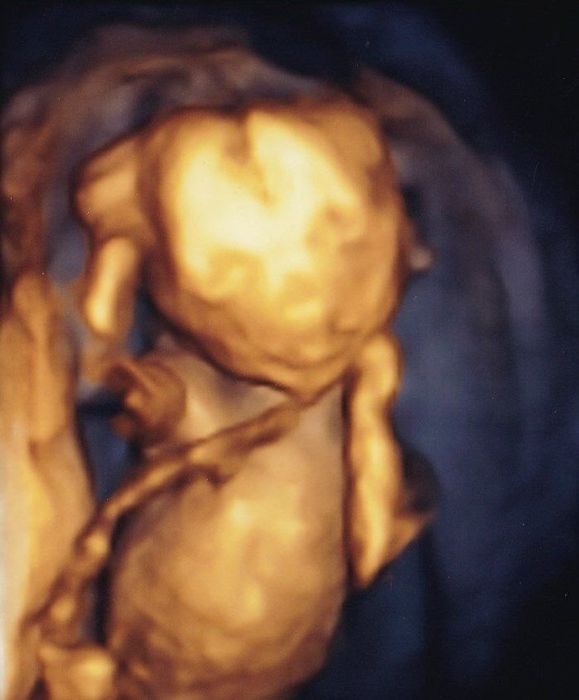

妊娠28週目の4Dエコー写真 私のおなかを苦しめる、ちょっと大きめな赤ちゃん

推定体重=1465g

お顔をアップにした4D画像です。うつむき加減で眠っているように見えました。赤ちゃんは順調に大きくなり、これ以降、毎回「ちょっと大きめですね」と言われるようになります。実際、おなかも苦しくなってきて、パソコン作業がつらくなってきました。ちょうど真夏の時期で、外出がとてもつらかったのを覚えています。